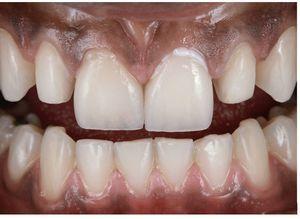

Se retira el dique de goma y se corrige la oclusión mediante un sistema de pulidores de diamante para cerámica. El tejido gingival sano estaba estable al cabo de dos semanas (figs. 35 y 36). Las figuras 37 y 38 muestran la sonrisa del paciente seis meses después del cementado.

Fig. 36. La situación al cabo de tres meses.

Figs. 37 a 40. La situación final al cabo de seis meses.